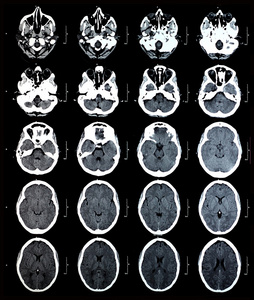

脑ct分析及病情变化分析